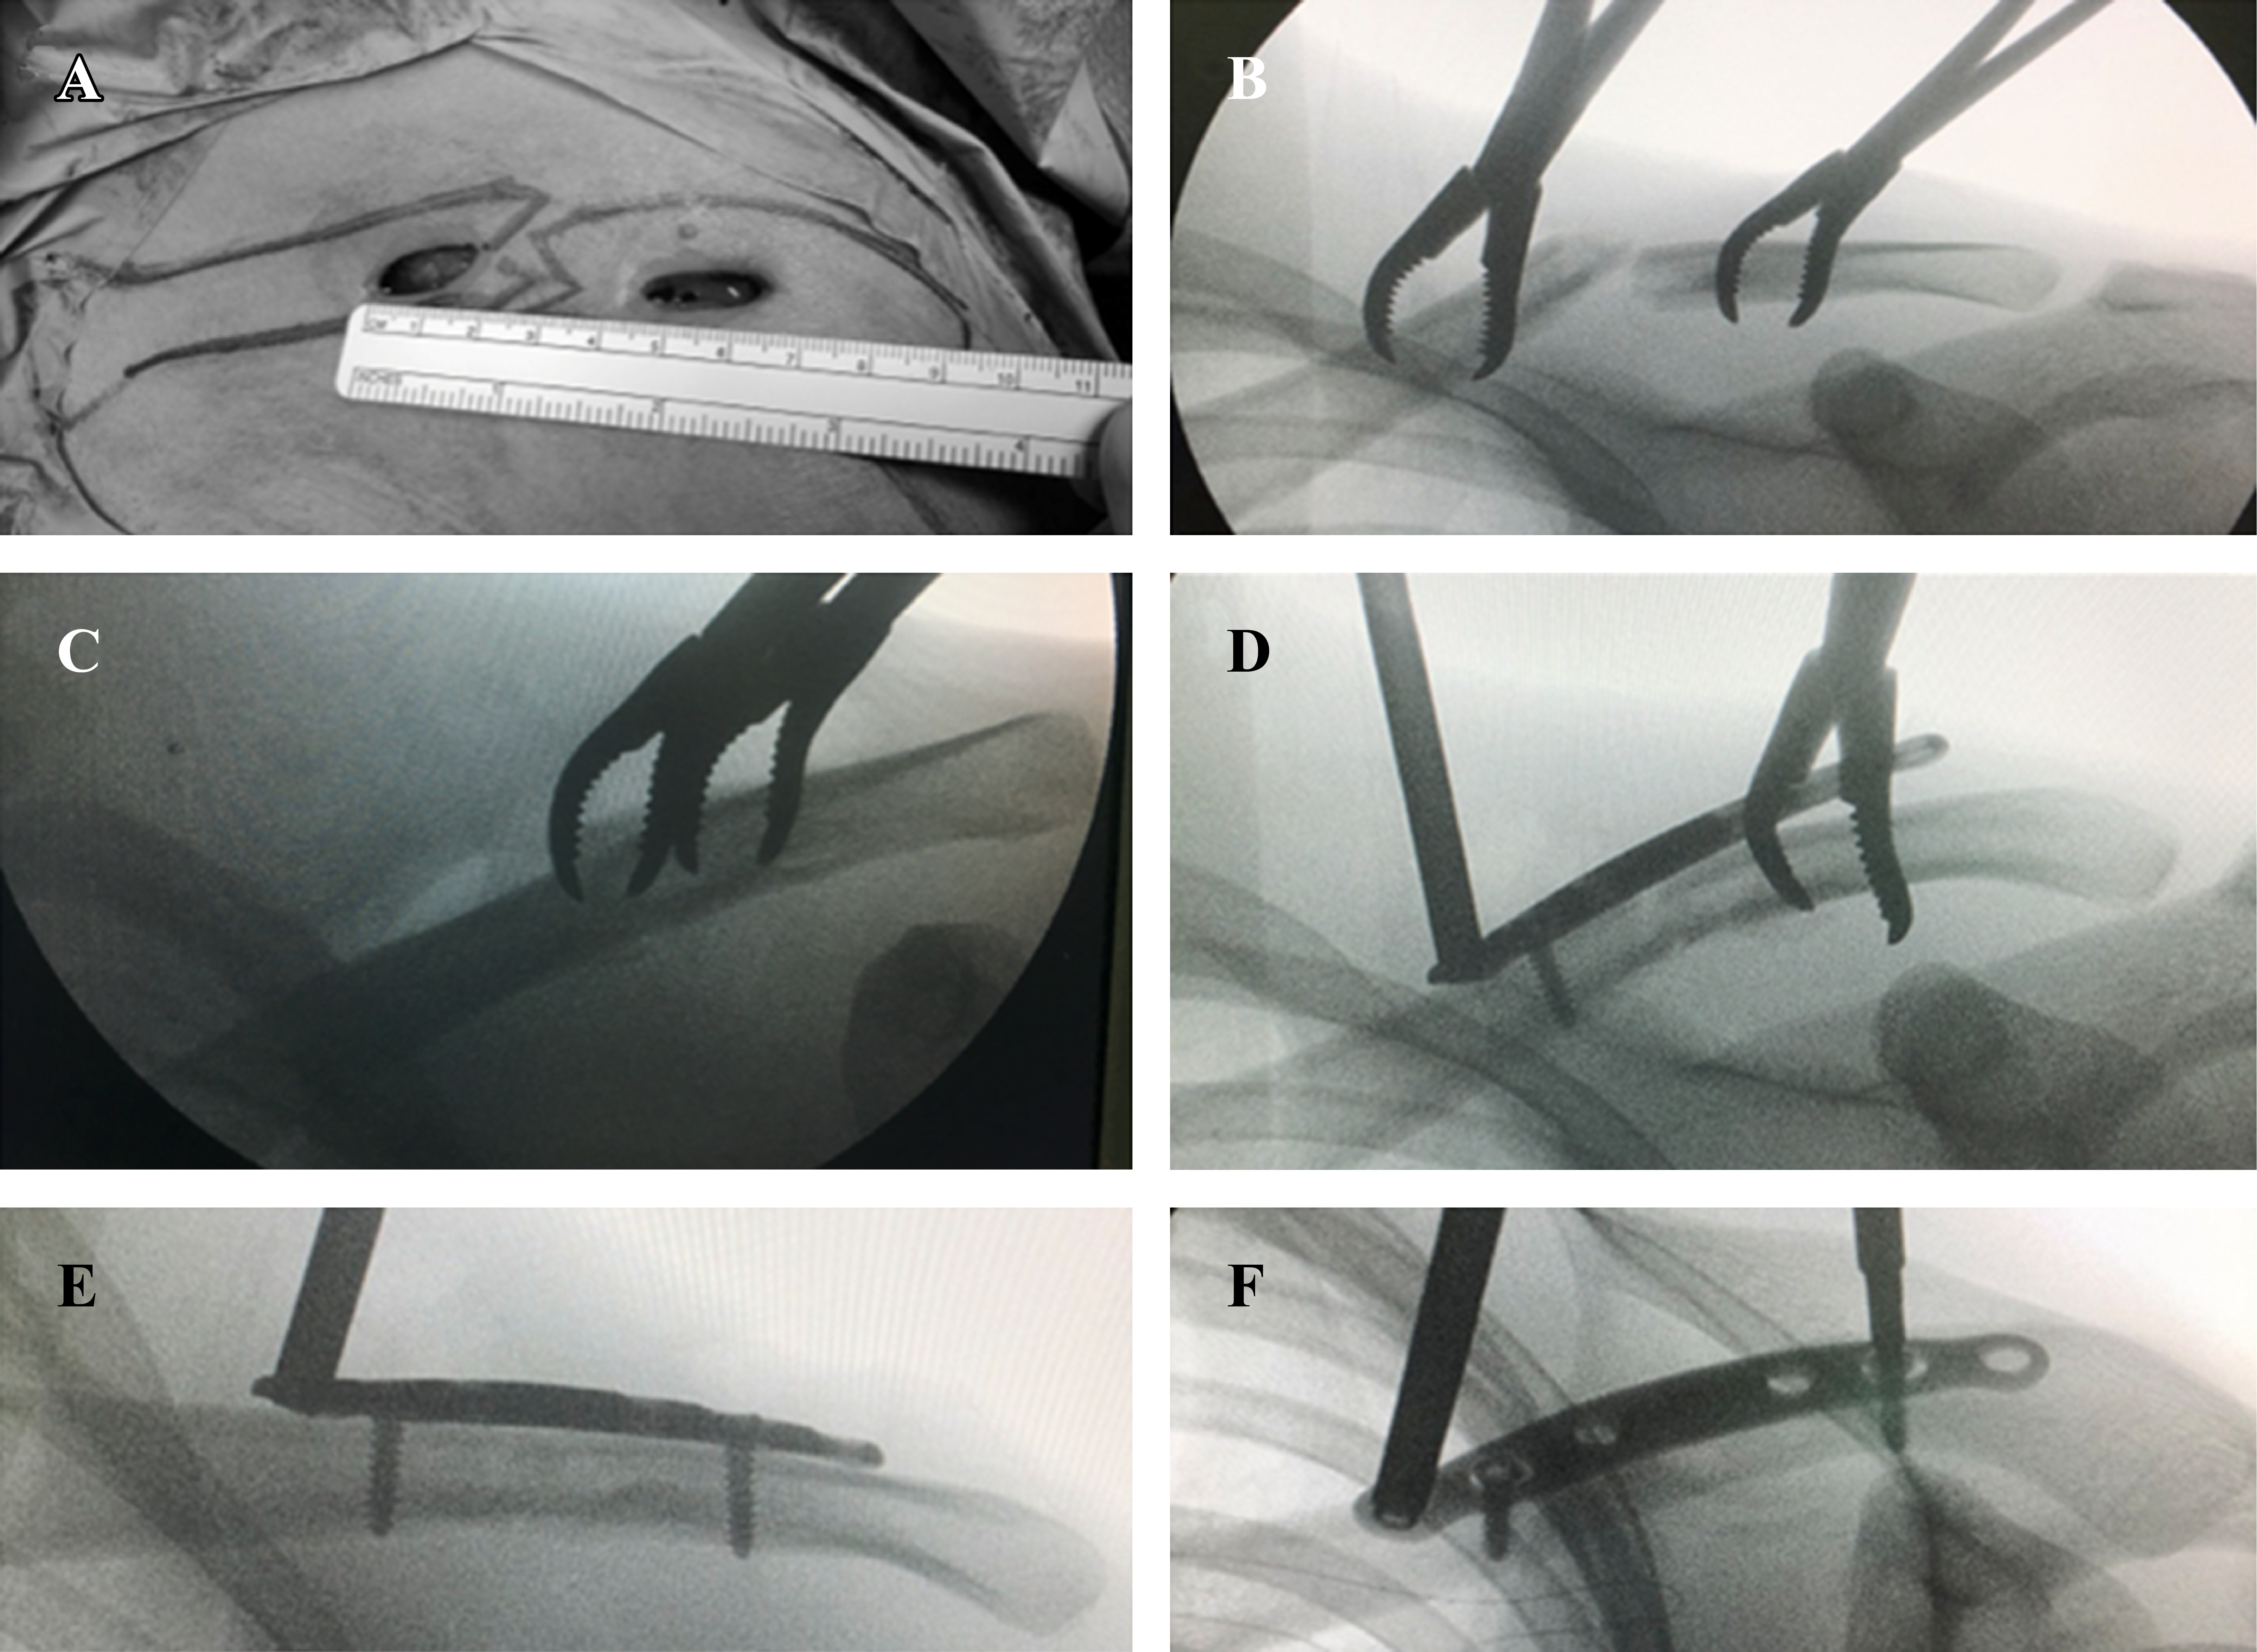

Posteriormente se realizan las respectivas incisiones cutáneas, respetando la piel sobre el foco de fractura y disecando con electrobisturí hasta el plano óseo (Figura 3A). Con ayuda de un desperiostizador se efectúa un estuche perióstico alrededor de cada fragmento óseo y un túnel submuscular entre ambos, justo sobre la clavícula a nivel del foco de fractura. A través de las incisiones y con ayuda de dos pinzas de reducción se realiza una reducción instrumentada de la fractura (Figura 3B y C). En este punto es posible efectuar una fijación transitoria para ayudar a mantener la reducción mediante el uso de una aguja Kirschner o una pinza de reducción tipo Backhaus. Utilizando una torre de bloqueo fija a un extremo de la placa, ésta se desliza en forma submuscular fijándola transitoriamente a ambos lados de la fractura con pinzas de reducción y/o agujas de Kirschner. Una vez obtenido un adecuado posicionamiento bajo fluoroscopía de la placa en el plano mediolateral y anteroposterior, se fija definitivamente el fragmento proximal y luego el distal con un tornillo bicortical no bloqueado central a cada lado de la fractura, para luego bloquear el constructo mediante la colocación de un tornillo de bloqueo a cada lado de los tornillos corticales (Figura 3D-F). En la Figura 4 se esquematiza una configuración de tornillos recomendable para este tipo de fracturas. Una vez completada la fijación con tornillos se comprueba que exista una adecuada reducción de la fractura así como un satisfactorio posicionamiento de la placa y largo de los tornillos en al menos dos planos ortogonales entre sí (Figura 5). Por último, se procede al cierre del plano muscular y subdérmico, utilizando suturas cutáneas reforzadas para la piel (Steri-Strip™; 3M®) más una cobertura con dos apósitos impermeables transparentes (Opsite™; Smith and Nephew®) (Figura 6).